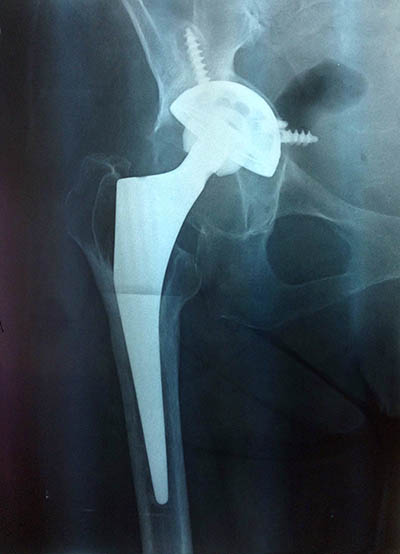

Mi è stata indirizzata da un collega fisiatra a causa di dolore, zoppia e in seguito ad una radiografia che evidenziava mobilizzazione del cotile con sfondamento dell’acetabolo. rx pre-operatoria art

E’ un caso da studiare accuratamente in quanto essendo state utilizzate delle viti per ancorare meglio il cotile all’osso del bacino durante il primo intervento queste ultime potrebbero essere migrate fino ad entrare in contatto con delle strutture “nobili”. Quindi faccio eseguire angiotac del bacino che evidenzia in effetti una stretta vicinanza tra una vite e un ramo dell’arteria ipogastrica.

Quindi ho utilizzato dell’osso di banca tritato cercando di ricostruire il fondo rx post-operatoria artdell’acetabolo su cui ho fissato con 3 viti un cotile in tantalio che ha un altissimo potere di osteointegrazione. Lo stelo appariva ben integrato quindi decido di non cambiarlo.